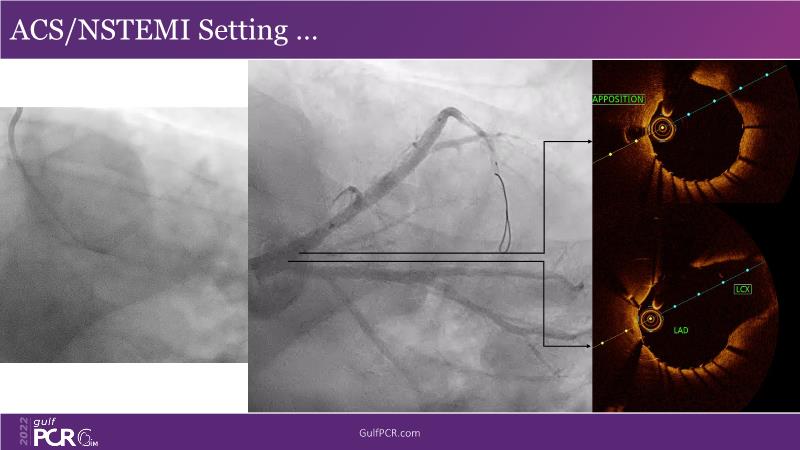

In this session, follow a LIVE case from the Chest Diseases Hospital in Kuwait and learn what the best strategy is to treat patients who present with a very long calcified coronary artery lesion, as well as how to select the best device and which different types of stents can be used.

- To understand value of intracoronary imaging in patient treatment